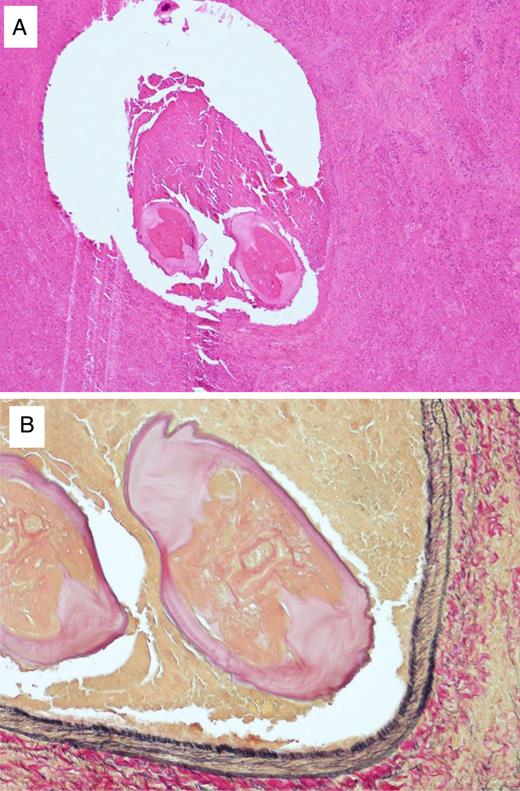

A 59-year-old Japanese man visited our hospital in April 2013 for a workplace medical examination. He was a former smoker (from 20 to 26-year-old, 1 pack per day), and had neither physical symptoms nor family history of malignancies. The chest X-ray did not detect an abnormal shadow, but a CT showed a mass with an irregular margin measuring 18 × 15 mm in diameter at the subpleural area of S9 of the right lower lobe (Fig. 1). The CT detected no nodules in the other lobes or regional lymph nodes swelling. A FDG-PET was performed, but did not yield a definitive FDG accumulation (data not shown). Such tumor markers as CEA, SLX, SCC, CYFRA, NSE, and ProGRP were all within their normal ranges. In May 2013, a lung partial resection was performed under video-assisted thoracic surgery (VATS). At the time of thoracotomy, the mass located at the periphery of S9 of the right lower lobe and the surface was whitely transparent (Fig. 2A). The mass was solid and hard on palpation (Fig. 2B). The intra-operative pathological findings (frozen section) revealed inflammatory granuloma with coagulation necrosis. The permanent pathological examination showed occlusion of the peripheral pulmonary artery by worms and formation of a necrotic mass surrounded by reactive inflammatory cells and hemorrhage in hematoxylin–eosin stain (Fig. 3A) and Elastica van Gieson stain (Fig. 3B). Post-operative course was uneventful, and he is doing well 15 months after surgery.

(A) Histopathological findings of the pulmonary nodule. Two transverse sections of an immature worm were seen in the peripheral pulmonary with fibrous tissue, necrotic tissue, and granulation (hematoxylin and eosin staining, ×6). (B) The transverse section in the peripheral pulmonary revealed layers of cuticle, internal longitudinal cuticular ridges and lateral chords, being identified as Dirofilaria immitis (Elastica van Gieson stain, ×20).